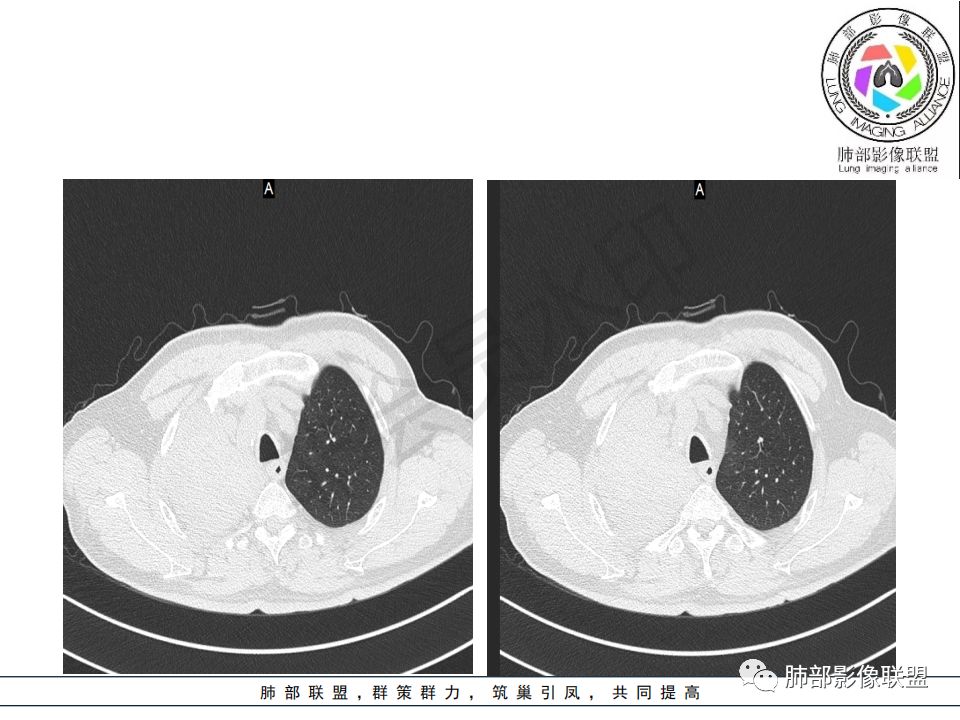

右肺主支气管内外软组织影,支气管变窄截断,右肺上叶成软组织密度,其内见细沙样钙化,周围看见小结节,右肺门看见一淋巴结稍大,增强不均匀强化,胃癌病史,考虑:转移,或原发肺恶性鳞癌。

晨读:患者老年男性,以咳嗽一月就诊,少量白痰,胸CT:纵隔右移,右肺体积缩小,气管下段管壁可见结节样改变,气管软骨变形,气管下段及右主支气管可见新生物向管壁浸润,并向管腔外生长,右上肺肺不张,但不张边缘可见病灶呈膨胀性生长,可见分叶,增强后强化明显。考虑:肺部恶性病变(鳞癌?)

晨读病例:老年男性,症状轻,右侧胸廓略塌陷,右肺主支气管内外软组织影,支气管变窄截断,右肺上叶不张,其内见细砂样钙化,周围看见小结节,右肺门看见一淋巴结稍大,增强不均匀强化,胃癌病史,常规考虑:转移,或原发肺恶性鳞癌。鉴别支气管TB?

@曹坤,河北保定清苑区人民医院ct室 肿块大,阻塞和不张范围小,强化这么大肿块没有明显坏死,鳞癌这样相对少见了

@刘鋆(福州长乐区医院)影像科 转移啊,腔外都在生长,部分通过支气管壁进入腔内

@刘鋆(福州长乐区医院)影像科 先转移生长到外面,然后进入腔内生长,也是外朝内一种,与平时那种外朝内生长逐渐侵犯近端气管没有太多区别,只不过这个是转移而已。

病理结果:腺癌,考虑来源消化道